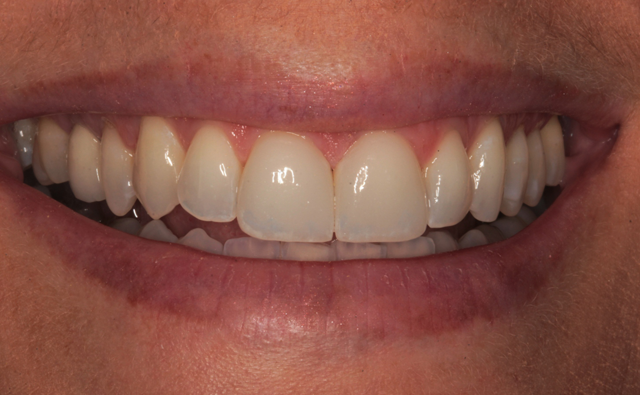

The final result is shown from the incisal view in Figure 27. The facial view after treatment can be seen in Figure 28. The patient's new smile is shown in Figure 29.

By using team treatment, Peter and I were able to achieve a superb color match with ceramic veneers that mimicked the appearance the surrounding neighbors. It was my job to prepare the teeth properly, acquire accurate impressions, provide excellent photography, choose a shade and deliver the finished laminates. Peter's job was to pour accurate models, produce the ceramic veneers and develop the color and contours to achieve the esthetic result.

Fig. 29